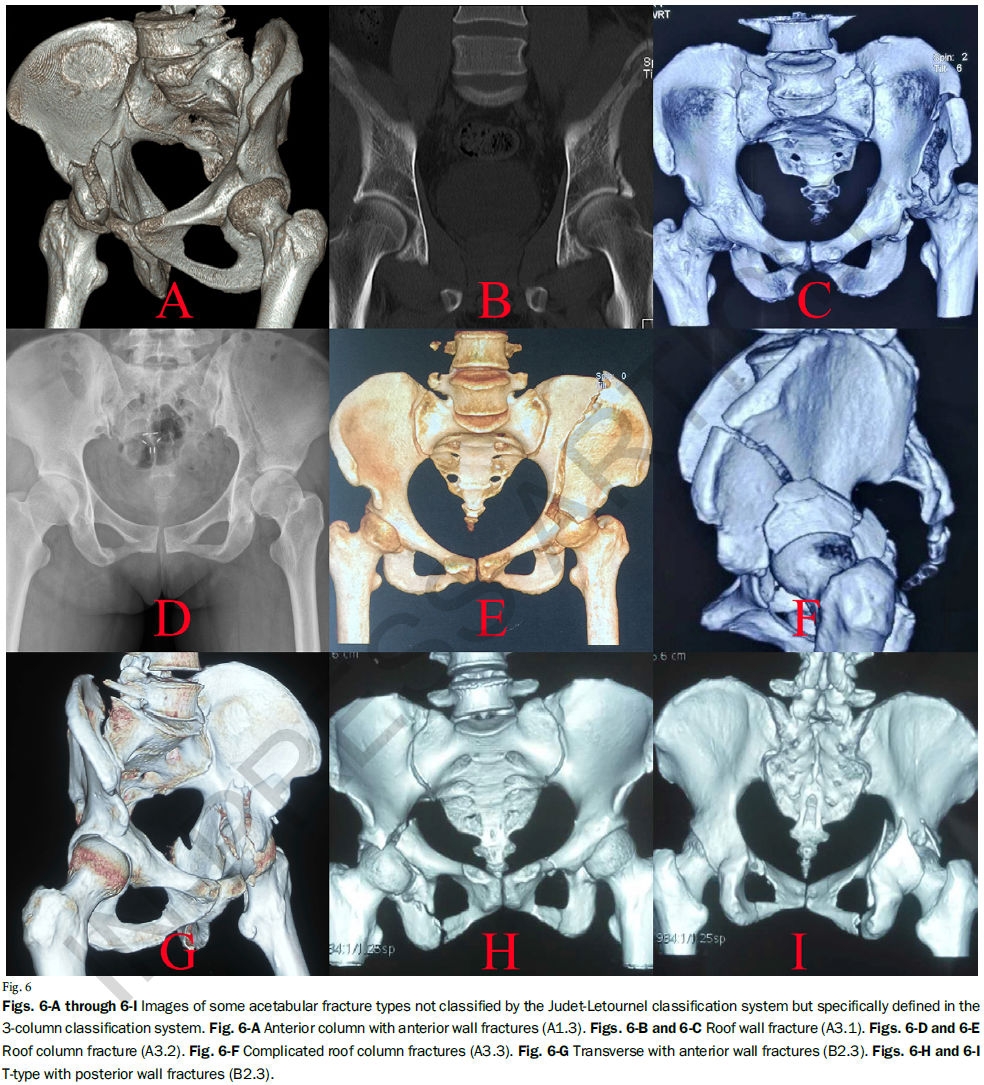

Letournel-Judet分型基于双柱理念将髋臼骨折分为5型简单、5型复杂骨折,已成为髋臼骨折诊断中最为常用的分型系统。然而,该分型存在包括不全、难以理解、容易混淆等弊端,充分掌握该分型需要较长的学习曲线;且其并未对各类型骨折的治疗提供指导,故其临床应用存在一定的局限性。

河北医科大学第三医院张英泽院士、侯志勇教授团队基于髋臼的解剖结构提出了髋臼骨折的三柱分型,将髋臼骨折分为单柱骨折、两柱骨折、三柱骨折三大类。该分型囊括骨折类型多、分型规律性强,解决了Letournel-Judet分型中的诸多问题,便于初学者掌握。

通过两种分型系统对来自七个一级创伤中心的1028例髋臼患者进行对比研究,显示三柱分型具有更高的一致性和可重复性;且基于该分型的手术入路具有很好的规律性,可为骨科同仁手术的选择提供参考。国内外学者一致认为该分型是对传统髋臼骨折分型的颠覆性创新,可能会成为创伤骨科领域程碑式的进展。